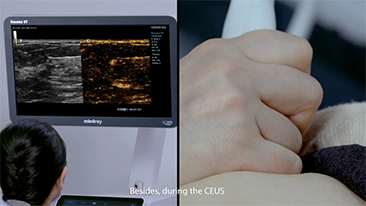

Per le lesioni focali epatiche, come l'emangioma o il tumore al fegato, l'imaging di contrasto a ultrasuoni svolge un ruolo importante. La tecnologia di imaging di contrasto Ultra-wideband non-linear UWN+ consente di ottenere una migliore penetrazione, un rapporto contrasto-tessuto pi├╣ elevato con un indice meccanico pi├╣ basso e un'osservazione del tempo di perfusione pi├╣ lunga.

A causa del Coronavirus, gli ospedali e il personale medico hanno sviluppato nuove pratiche di lavoro che comportano, nei contesti di assistenza acuta, il distanziamento sociale, l'uso rigoroso di dispositivi di protezione individuale (DPI), il lavaggio delle mani e la disinfezione quotidiana delle attrezzature. Le apparecchiature portatili, altamente mobili e versatili sono diventate sempre pi├╣ richieste nei punti di cura (POC), in particolare quando i reparti e le sale operatorie sono distribuiti su pi├╣ piani e lŌĆÖutilizzo di dispositivi specialistici ├© importante.